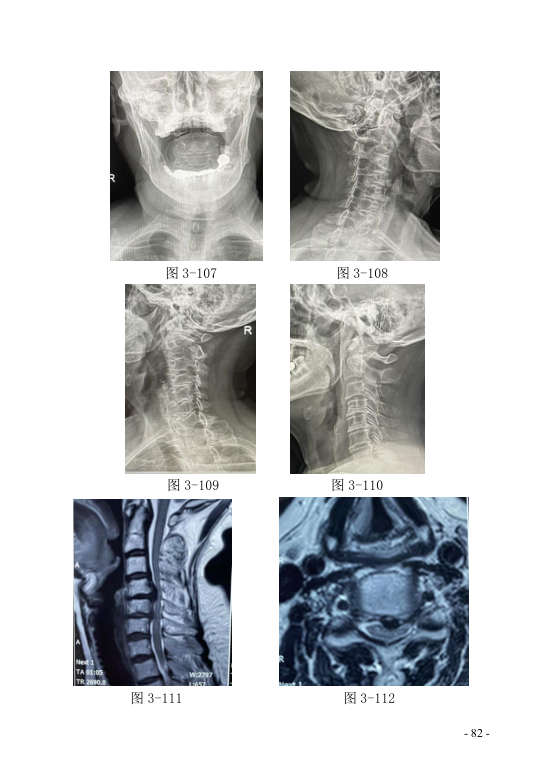

十四、颈椎手术失败综合征-------------- 83